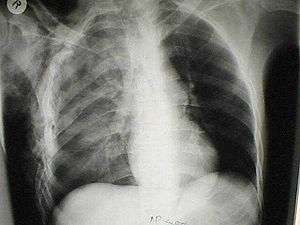

Pulmonary laceration may not be visible using chest X-ray because an associated pulmonary contusion or hemorrhage may mask it.[1][9] As the lung contusion clears (usually within two to four days), lacerations begin to become visible on chest X-ray.[3] CT scanning is more sensitive and better at detecting pulmonary laceration than X-rays are,[1][4][14][17] and often reveals multiple lacerations in cases where chest X-ray showed only a contusion.[14] Before CT scanning was widely available, pulmonary laceration was considered unusual because it was not common to find with X-ray alone.[14] On a CT scan, pulmonary lacerations show up in a contused area of the lung,[9] typically appearing as cavities filled with air or fluid[18] that usually have a round or ovoid shape due to the lung's elasticity.[6]

Hematomas appear on chest radiographs as smooth masses that are round or ovoid in shape.[1] Like lacerations, hematomas may initially be hidden on X-ray by lung contusions, but they become more apparent as the contusion begins to heal.[1] Pneumatoceles have a similar shape to that of hematomas but have thin, smooth walls.[19] Lacerations may be filled completely with blood, completely with air, or partially with both.[6] Lacerations filled with both blood and air display a distinctive air-fluid level.[6] A single laceration may occur by itself, or many may be present, creating an appearance like Swiss cheese in the radiography of the lung.[6]

A healing laceration may resemble a pulmonary nodule on radiographs, but unlike pulmonary nodules, lacerations decrease in size over time on radiographs.[6]